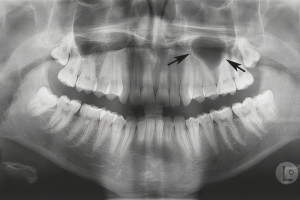

Радиационно-индуцированный некроз или остеорадионекроз характеризуется наличием обнаженной кости после проведения лучевой терапии. Открытая кость может полностью секвестрировать, что часто приводит к обнажению большего количества кости. Хотя кость, расположенная в любом месте челюсти, восприимчива к излучению, задняя часть нижней челюсти поражается чаще, чем другие области, потому что она часто находится в поле излучения, особенно когда в лечение включены лимфатические узлы. Может возникать интенсивная боль при периодическом отеке и дренировании вне полости рта. Однако многие пациенты не чувствуют боли при обнажении костей. Утрата нормальной структуры может нарушить целостность кости, а в некоторых случаях кость может сломаться.